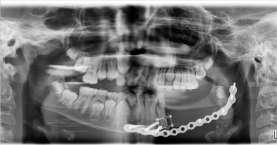

Underkäkenpåenkirurg

Namn: Fredrik Holmqvist

Titel: Övertandläkare inom kirurgi, Doktorand

Tandläkarexamen: Karolinska

Institutet år 1996

Det finns olika inställning inom vår bransch gällande vad som är den viktigaste egenskapen för en bra käkkirurg. För min del anser jag att en bred kunskap och förståelse för odontologin är den unika grund som gör oss till bra käkkirurger.

Vilken utveckling inom käkkirurgin tycker du är mest spännande just nu?

Arbete med digitalt stöd för planering av operation och arbetet med att bekämpa mikrobiell resistensutveckling

Hur ser du på framtidens käkkirurgi –vad tror du kommer att förändras mest de kommande åren?

Jag tror att man inom offentlig sektor kommer behöva fundera på hur man ska kombinera möjligheten att erbjuda arbete inom både offentlig och privat sektor Ett problem vi ser är att framför allt seniora, men även yngre kollegor, tröttnar på att arbeta inom offentlig sektor då möjligheten att själv styra sitt arbete med goda förutsättningar för hög inkomst lockar i kombination med att slippa arbeta obekväm arbetstid Det finns ju också en vilja att införa mer medicinsk kompetens inom området, och där har man ingen nationell samsyn gällande hur detta bör fungera Ett ökat samarbete med både tand- och sjukvård framför allt xxxx